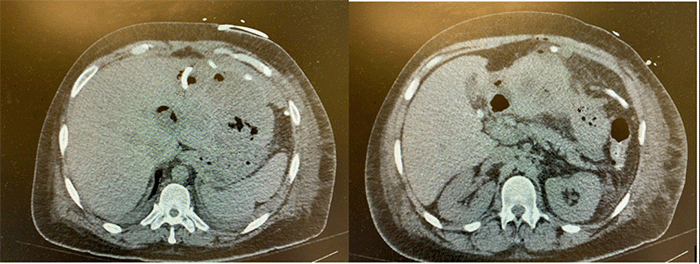

Figure 4. Follow-up CT Showing Resolution of Hepatic Abscess. Published with Permission

Axial contrast-enhanced CT scan of the abdomen obtained after completion of antimicrobial therapy and outpatient drain management. Note significant interval improvement with resolution of the previously identified left hepatic lobe abscess